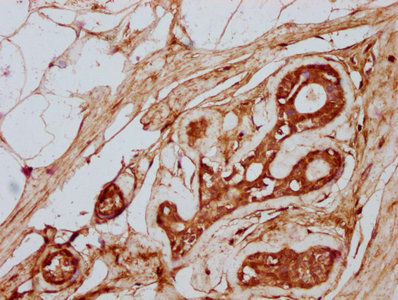

IHC image of CSB-PA23329A0Rb diluted at 1:300 and staining in paraffin-embedded human prostate cancer performed on a Leica BondTM system. After dewaxing and hydration, antigen retrieval was mediated by high pressure in a citrate buffer (pH 6.0). Section was blocked with 10% normal goat serum 30min at RT. Then primary antibody (1% BSA) was incubated at 4°C overnight. The primary is detected by a biotinylated secondary antibody and visualized using an HRP conjugated SP system.

IHC image of CSB-PA23329A0Rb diluted at 1:300 and staining in paraffin-embedded human breast cancer performed on a Leica BondTM system. After dewaxing and hydration, antigen retrieval was mediated by high pressure in a citrate buffer (pH 6.0). Section was blocked with 10% normal goat serum 30min at RT. Then primary antibody (1% BSA) was incubated at 4°C overnight. The primary is detected by a biotinylated secondary antibody and visualized using an HRP conjugated SP system.